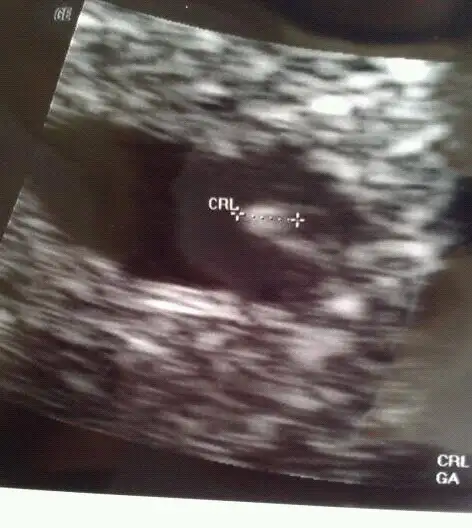

Sosyalcim benim pzrts sata göre 6+3 ken dr. 5+6 dedi, bebişi gördük kalp atışını dinledik :) hcg değerim o gün 6200 küsürdü b arada.. Bende bebişin fotosunu eklicem şimdi,, becerebilirsem tabi ;)

Bak bu benim bebişşş :)) evet dayananadım yaaa, sağol canım sen naptınnn

kaç haftalım cnm bu ultrason resmi

Tatlım bu sata göre 6+3, dr 5+6 dedi bu pazartesinin ;)